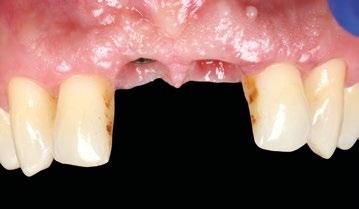

Se presenta el caso de un paciente varón de 48 años de edad, ASA II, fumador que acude a consulta por la pérdida de su incisivo central superior derecho (Figura 1).

A la exploración clínica se observa enfermedad periodontal estadio III grado B con múltiples ausencias dentarias posteriores de larga evolución que han ocasionado la migración de los dientes adyacentes y antagonistas generando múltiples prematuridades e interferencias. Como consecuencia de todo ello, el paciente ha perdido el diente 1.1 con pérdida de volumen de tejido y el 2.1 presenta movilidad grado III con pronóstico imposible (Figura 2).

En la exploración radiográfica en 3D (CBCT) se aprecia ausencia de cortical vestibular en 2.1 y un defecto óseo horizontal en 1.1 (Figura 3).

16

1

2